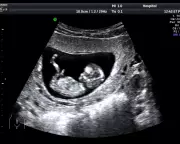

Anastasia Shubareva-Epshtein shares her traumatic experience of confirming a miscarriage in a London ultrasound clinic on Mother's Day, highlighting the lack of support for pregnancy loss.

RecommendedA mother shares her emotional IVF journey through secondary infertility, detailing failed transfers, immune testing, and ultimate success with a pregnancy at 40.

A fertility nutritionist shares her emotional journey through secondary infertility and multiple failed IVF transfers at age 40, culminating in a successful pregnancy.

Secondary infertility, the inability to conceive after having a child, is a growing but often overlooked issue affecting many families in the UK, with emotional and societal impacts.